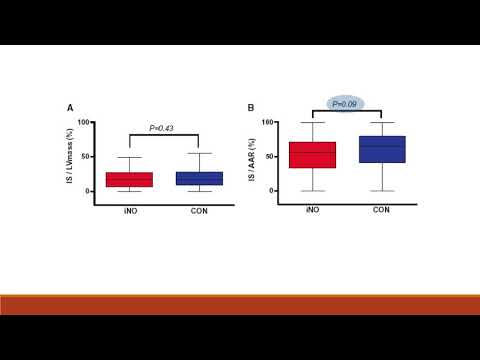

Óxido nítrico inhalado en IAMCEST. Dra. Eugenia Doppler. Residencia de Cardiología. Hospital C. Argerich. Buenos Aires